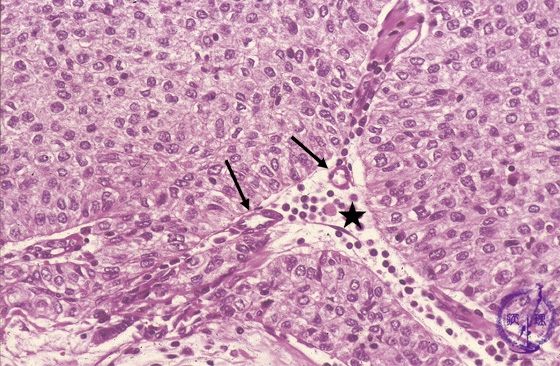

Microscopic view (high power view): Type B3 thymoma (epithelial thymoma) (WHO classification). Large, polygonal epithelial tumor cells grow in sheets without infiltrating lymphocytes. The perivascular spaces (★) seen centrally surrounding small capillaries (arrow) are a finding specific to thymoma.